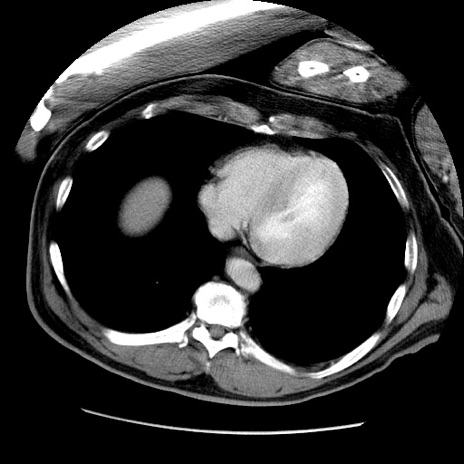

症例22(横断像)

【症例】50歳代男性

【主訴】腹痛

【現病歴】AVMからの被殻出血のため回復期リハ病棟入院中。 本日午後3時頃急に下腹部痛が出現した。

【既往歴】AVM、被殻出血、虫垂炎、高血圧

【身体所見】意識晴明、左半身不全麻痺、会話の理解は良好、36.5°C、腹部:膨隆、全体に板状硬、下腹部正中に圧痛点あり、反跳痛-、筋性防御不明、右下腹部にope scar

【データ】WBC 9400、CRP 0.06